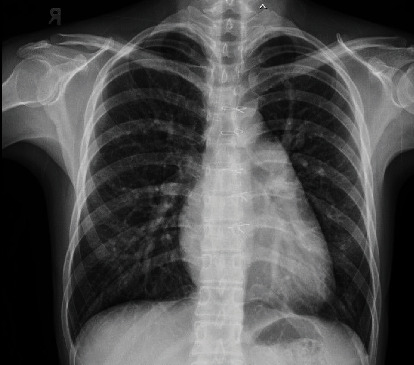

下静脉窦缺损(SVD)较上静脉窦缺损少见。缺损的下缘横跨下腔静脉口,这使得通过双腔静脉插管进行手术修复成为一项技术挑战。无顶右肺静脉的开口是由静脉窦缺陷的房间交通引起的,导致部分肺静脉异常引流(PAPVD)。最近报道了一种新型经导管闭合上位SVD;然而,经导管关闭下位SVD尚未在已发表的文献中报道。在这里,我们报告了首例成功的经导管关闭下静脉曲张,使用裸露和覆盖支架,并将PAPVD重新定向到左心房,以避免肝静脉闭塞。在这一单例报告中,我们仔细地描述了计划过程,手术是如何进行的,以及重新捕获和重新定位迁移支架所采取的步骤。在手术前和手术过程中,仔细选择患者并对肺和肝静脉解剖进行深入评估是取得成功的必要条件。

Inferior sinus venosus defect (SVD) is less common than a superior one. The lower edge of the defect straddles the orifice of the inferior vena cava, and this makes surgical repair via bicaval cannulation a technical challenge. The orifice of the unroofed right pulmonary vein is caused by the interatrial communication in sinus venosus defects which results in partial anomalous pulmonary vein drainage (PAPVD). Novel transcatheter closure of a superior SVD has recently been described; however, transcatheter closure of an inferior SVD has not yet been reported in the published literature. Here, we report the first successful transcatheter closure of an inferior SVD with bare and covered stents and the rerouting of a PAPVD into the left atrium to avoid occlusion of the hepatic veins. In this single-case report, we carefully describe the planning process, how the procedure was performed, and the steps taken to recapture and reposition a migrated stent. Careful patient selection and intensive assessment of pulmonary and hepatic vein anatomy before and during the procedure were necessary to achieve a successful outcome.